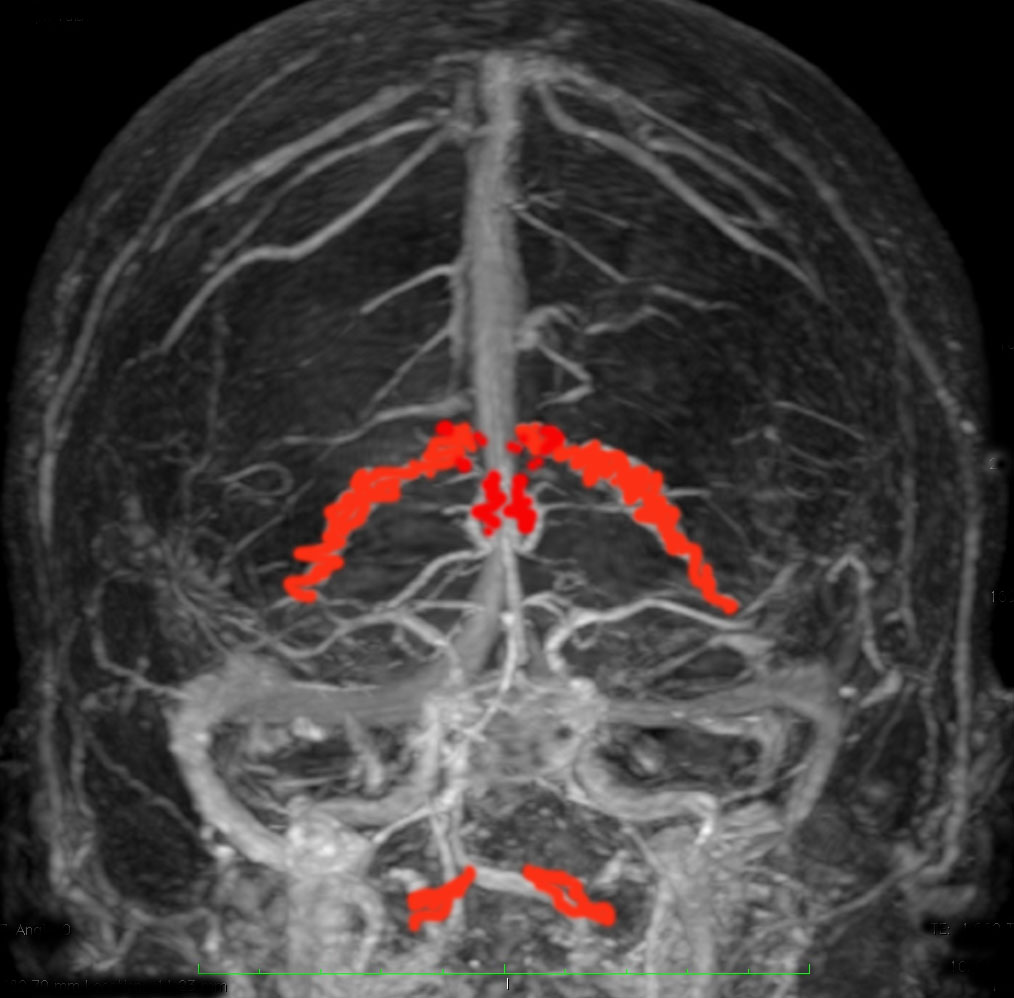

脳室内脈絡叢です(脳の静脈と一緒に描出しています)

正面から脈絡叢を見たところと左横から見たところ

- 髄液は脈絡叢(赤く塗ったところ)で作られます。

- 脈絡叢は側脳室と第3脳室と第4脳室にあります。下の方に離れているのが第4脳室のものです。

- 髄液 CSF cerebrospinal fluid は,くも膜顆粒 arachnoid granule から吸収されて,太い静脈に入り,心臓まで帰って行きます